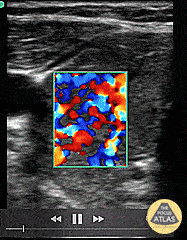

Soft Tissue - Thyroid Storm (Inferno Sign)

Thyroid Storm (Inferno Sign) Patient with a history of “glandular problems” as per the family presented from urgent care with confusion, slurred speech, tremors and fever. TSH was sent out. The patient was started on treatment for thyroid storm after color flow over an enlarged thyroid demonstrated the inferno sign. Patient improved on thyroid storm treatment. Infectious workup was negative. 48 hour T4 serial dilutions resulted at 2000. Dr. Dustin Morrow